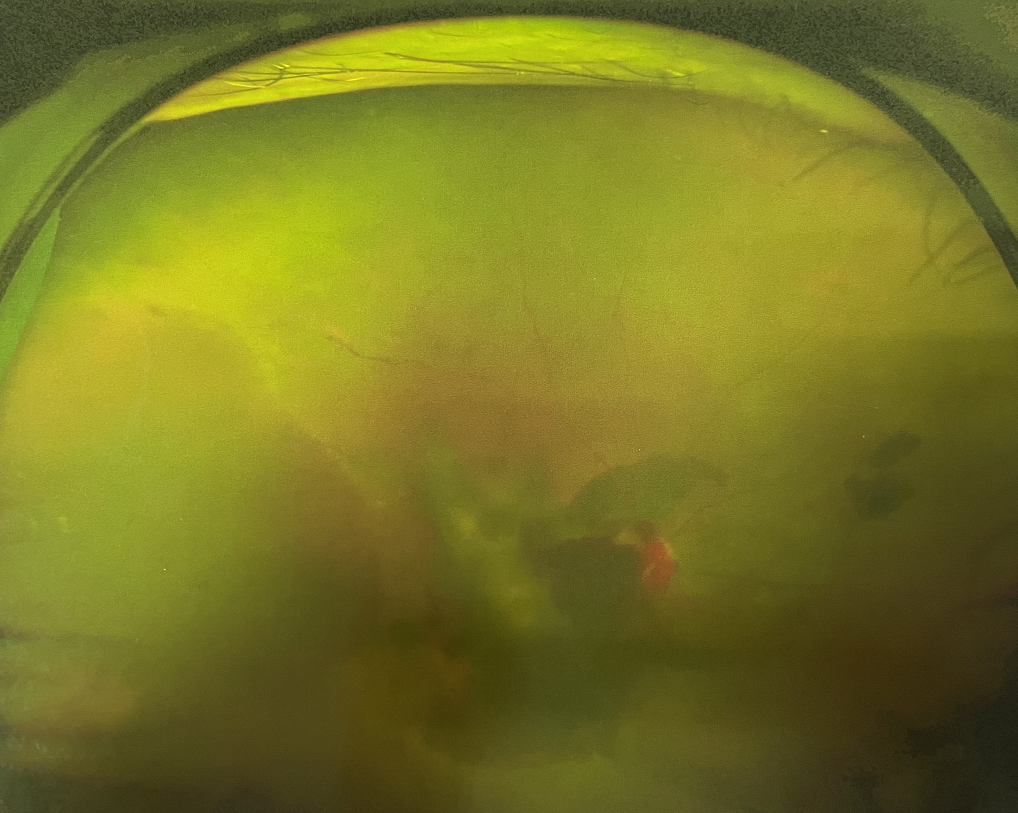

眼底出血雖然“看不見(jiàn)”,但嚴(yán)重可致盲!

眼底出血不是獨(dú)立的眼病,而是由于眼球自己的病變和某些全身疾病的并發(fā)癥導(dǎo)致眼底的視網(wǎng)膜或脈絡(luò)膜出血,如果出血量大就會(huì)進(jìn)入到眼球的玻璃體內(nèi),從而影響視力,如果沒(méi)有得到恰當(dāng)?shù)闹委熆蓭?lái)更嚴(yán)重的并發(fā)癥造成失明。

眼底出血的患者,如果出血量少,而且在視網(wǎng)膜周邊部可能沒(méi)有明顯癥狀,患者僅感到眼前有黑影浮動(dòng);如出血量多,將嚴(yán)重影響視力,甚至完全被黑影所遮擋僅剩光感;如出血位于視網(wǎng)膜的黃斑區(qū),患者視野中心區(qū)被暗影遮擋,周邊尚有部分視力。

先是散瞳檢查眼底,可以明確眼底出血的性質(zhì),出血部位和出血量有多少。眼B超檢查,對(duì)于眼底出血量特別多,無(wú)法看清眼底的患者,就需要進(jìn)行眼部B超檢查,以了解出血量,出血部位、有無(wú)合并視網(wǎng)膜脫離;還可以明確是否患有視網(wǎng)膜或脈絡(luò)膜的腫瘤。